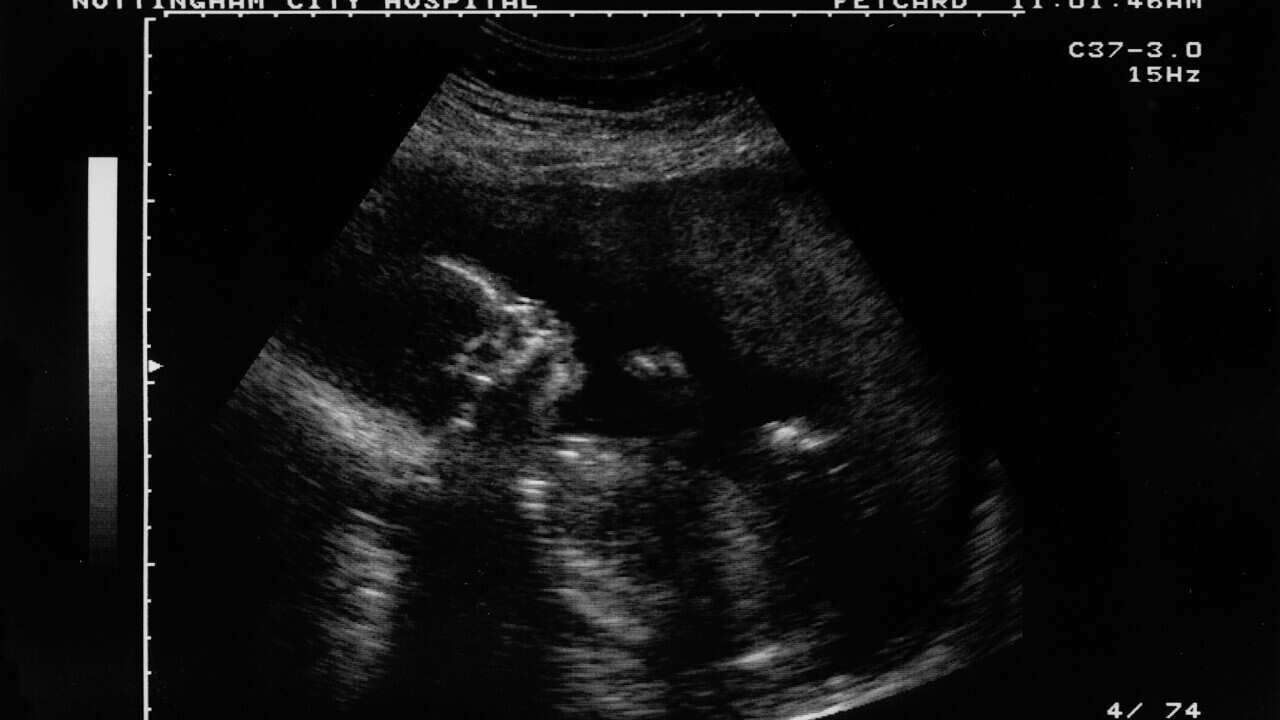

ప్రతి జంటకు పిల్లలు కావాలనే కోరిక ఉంటుంది. కానీ కొన్ని సందర్భాల్లో ఈ ఆశలు నెరవేరవు. ఇప్పటివరకు సరోగసి మాత్రమే ఒక పరిష్కారం ఉండేది. ఇప్పుడు, చైనాలో కృత్రిమ గర్భంతో ఇటీవల జరిపిన పరిశోధనల ఆధారంగా ఈ కోరికలు సాకారం చేసుకోవచ్చని నిపుణులు చెబుతున్నారు. కృత్రిమ గర్భం అంటే ఏమిటి, ఎలా పనిచేస్తుంది అనే విషయాలను ఈ శీర్షికలో తెలుసుకోండి.